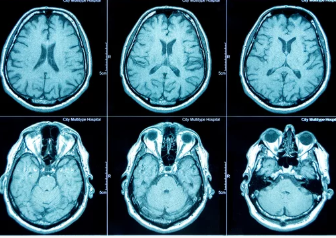

CT검사(Computed Tomography)는 X선을 이용해 인체를 단면으로 촬영한 후 컴퓨터로 3D 이미지를 재구성하는 방법입니다.

- 작동 원리: X선을 다양한 각도로 투사해 신체 내부의 단면 영상을 얻고, 이를 3D로 재구성합니다.

- 주요 사용 부위: 머리(뇌), 흉부(폐), 복부(간, 신장, 췌장), 심장 등.